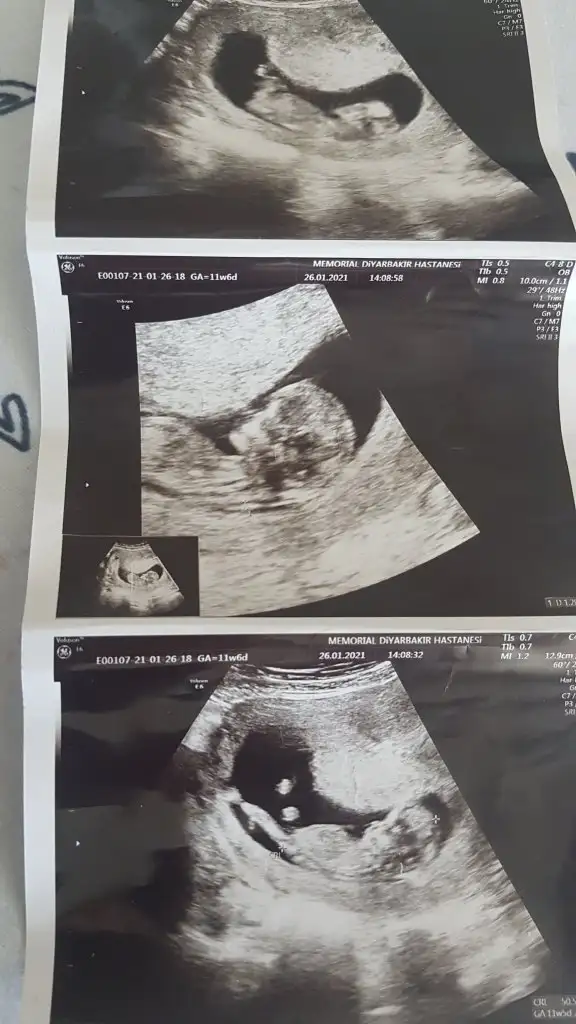

dün 2 li tarama testine girdim bebeğim uyuyordu doktor cinsiyet tahmini yapmadı renkli ultrasonografi görüntülerim var, bu resimlere göre cinsiyet tahmini yapabilirmsiiniz , bu ikinci gebeliğim 8,5 yaşında bir kızım var

mesajım görünmüyor mu acaba cevap alamadım, 12+5 de 2 li tarama yaptırdım, cinsiyet tahmini yapmadılar, bu görüntüler üzerinden tahmin yapabilirmisiniz

tebrik ederim doktor dahil kimsenin göremediğini siz görmüşsünüz 4. aydan sonra anladılar bebeğin erkek olduğunu

Yaaa çok teşekkür ederim 💙😍 sağlıkla gelsin oğlusun 🥰 anketim oylarsaniz sevinirim 🥰